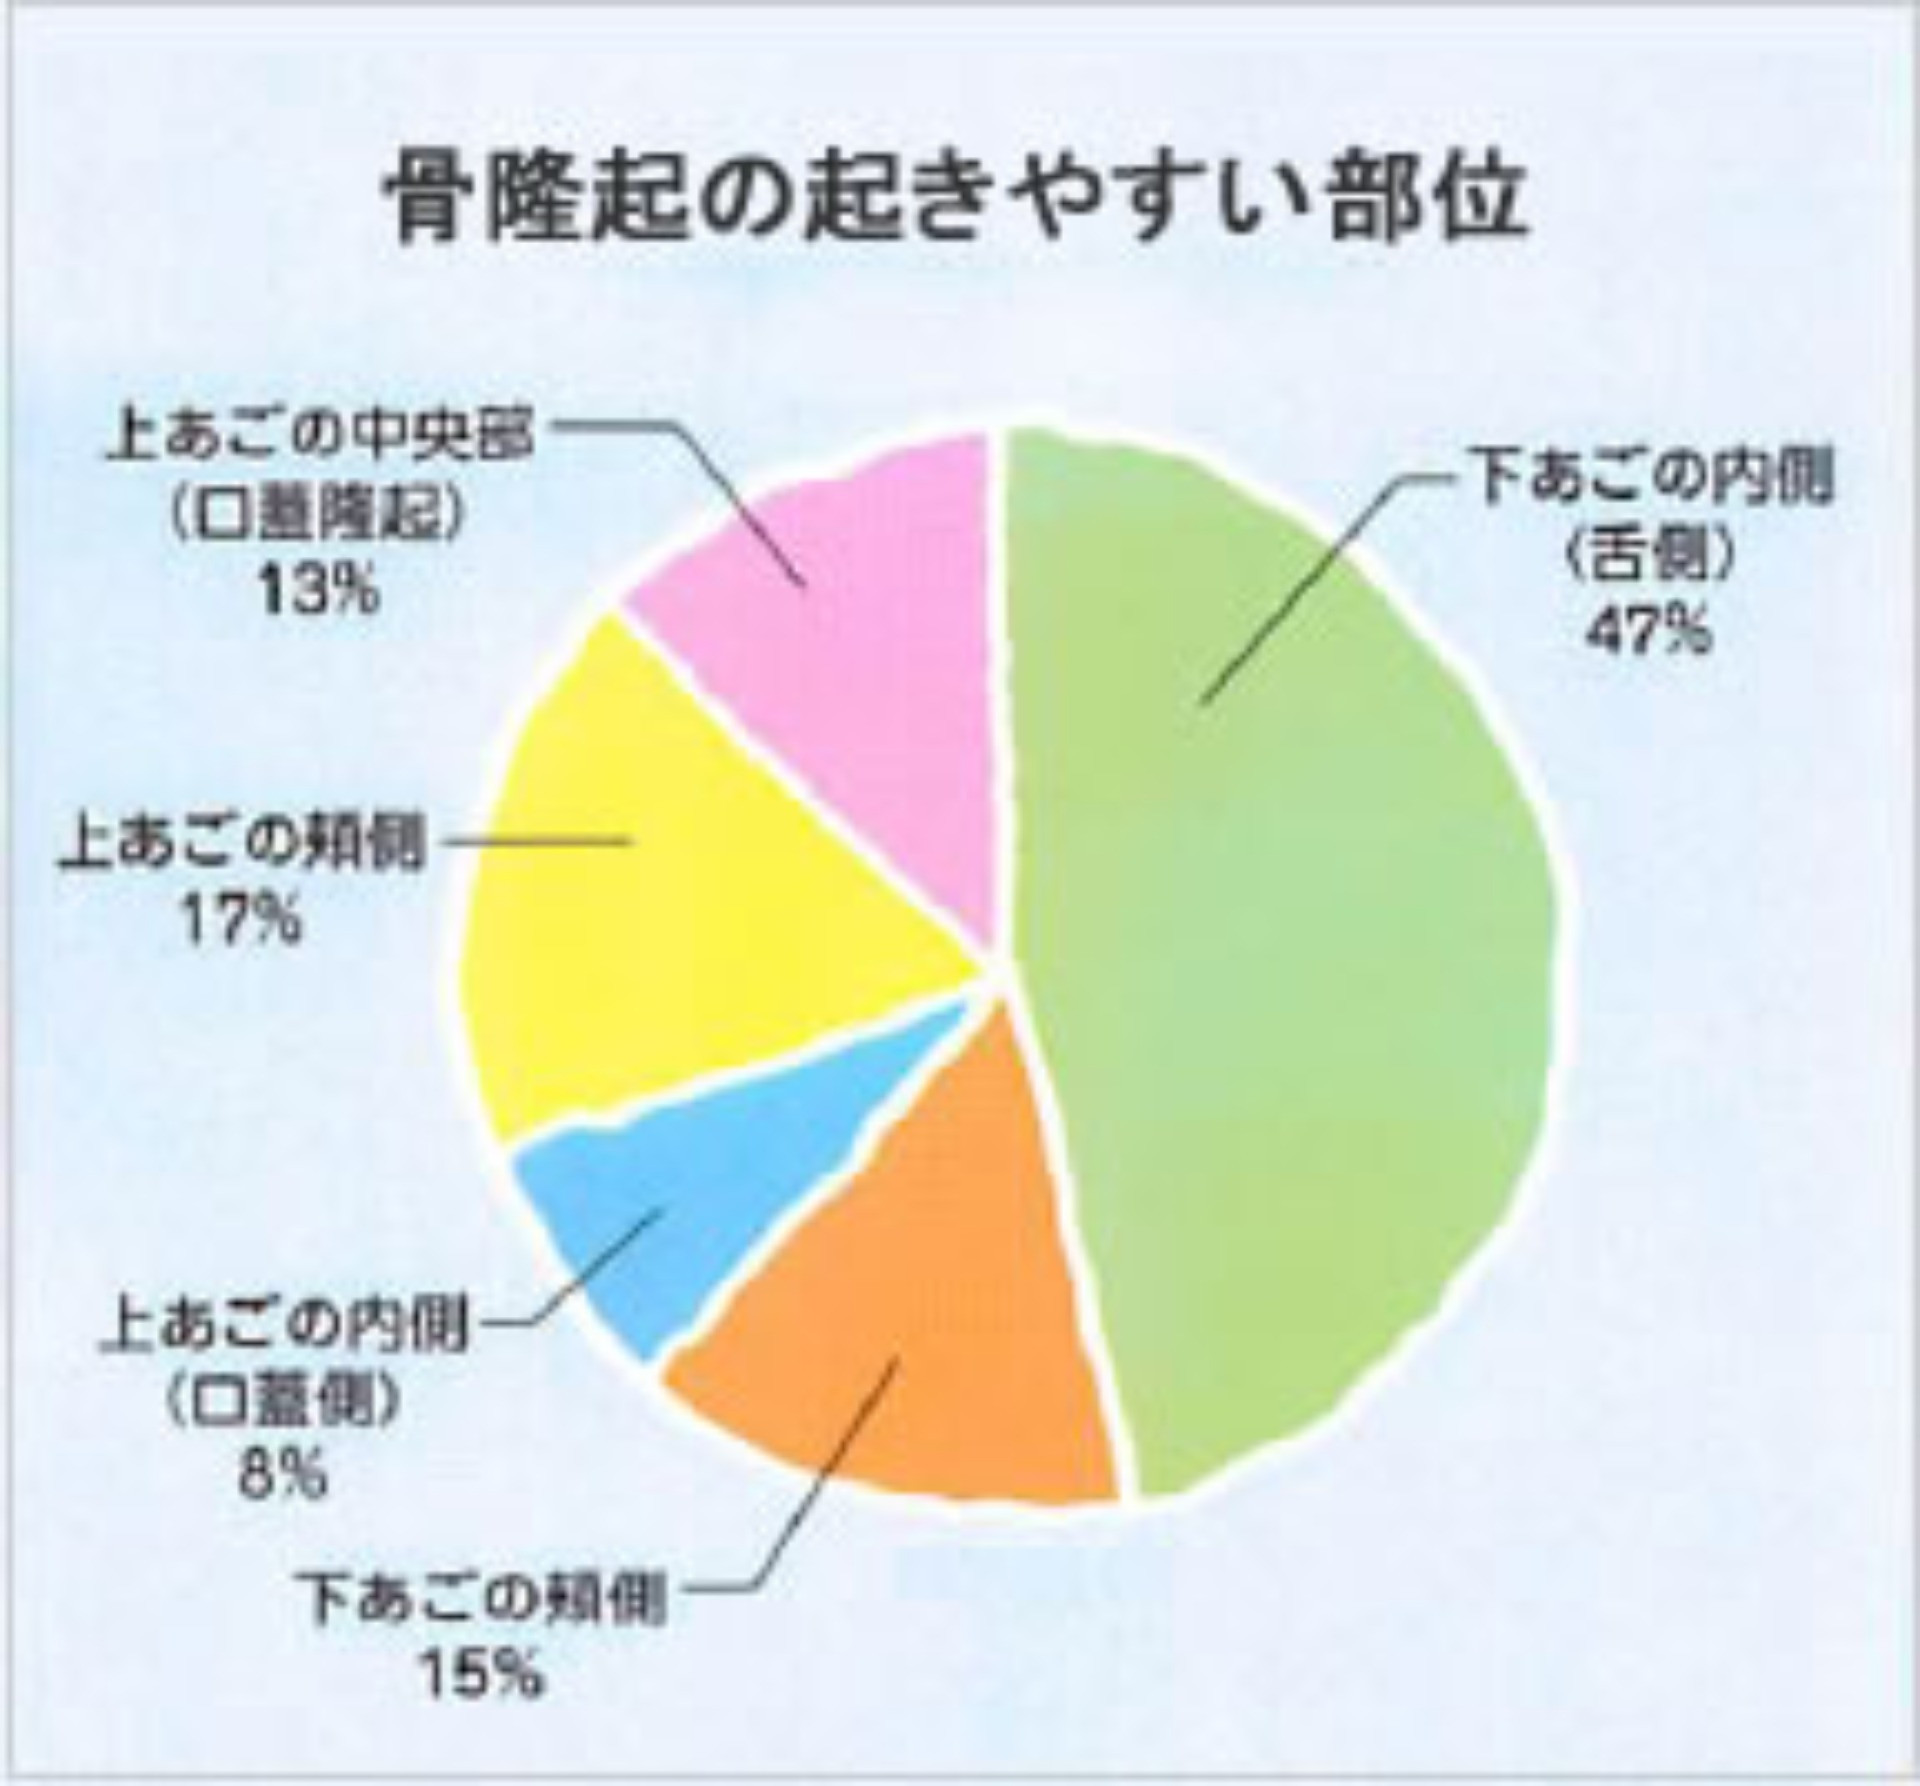

●骨の隆起:これって歯肉の腫瘍?

下の写真の矢印部は、歯ぐきが膨らんで触れると硬く、骨ばっています。これは遺伝や咬みあわせ、強い咬合力などにより、骨が部分的に増殖したもので、上あごの中央部、下あごでは犬歯の内側付近にできることが多いようです。病的なものではないので、問題がなければ取り除く必要はありませんが、入れ歯を作るのに障害になったり、食事に影響が出るような場合には、外科的に取り除きます。